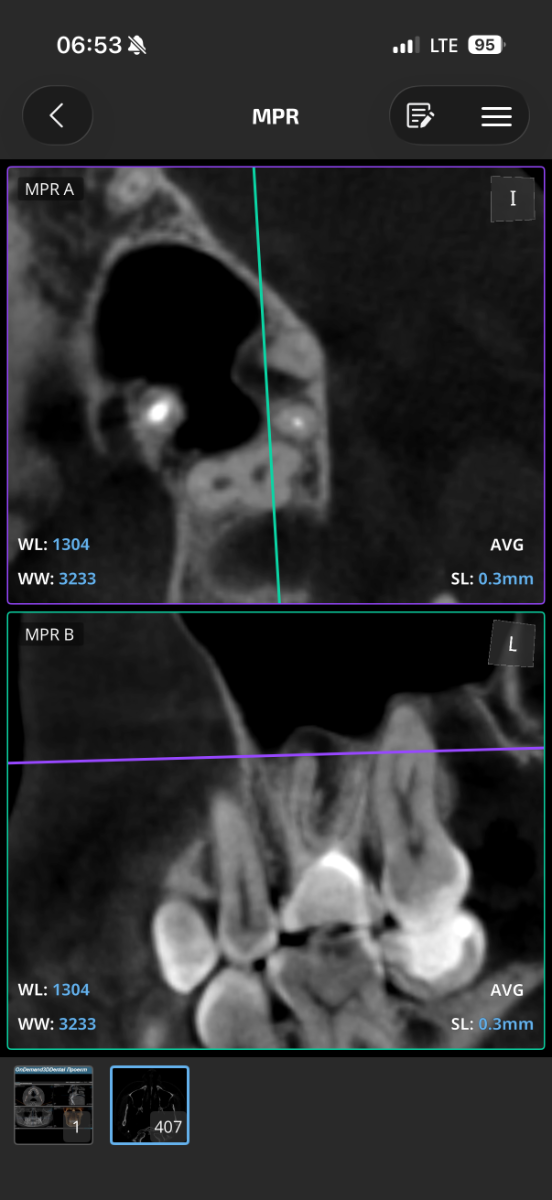

Добрый день, пожалуйста объясните что с зубом простыми словами, я если честно ничего не понял, там проблемы? Просто к стоматологу пойду через неделю только чтобы мне объяснили КТ, хочется сейчас узнать хоть что-то: 16 зуб эндодонтически лечен. Коронковая часть восстановлена рентгеноконтрастным материалом. Небный корень: канал широкий, обтурирован высококонтрастным материалом, верхушка корня не закрыта. Периапикально очаг деструкции костной ткани 4,5х4мм. запломбирован. Щёчно-медиальный корень – признаки дилацерации корня, канал запломбирован частично. Периапикально очаг деструкции 4х4мм Щёчно-дистальный корень: длина корня не более 4мм, в канале и за верхушкой корня определяется пломбировочный материал. Периапикально признаки деструкции костной ткани, очаг с нечеткими контурами. Жалоб на зуб вроде нет.. просто если очень долго вообще не жевать ничего или вообще челюстью не работать, при надкусывании чувствуется дискомфорт, но очень очень быстро проходит и больше не появляется